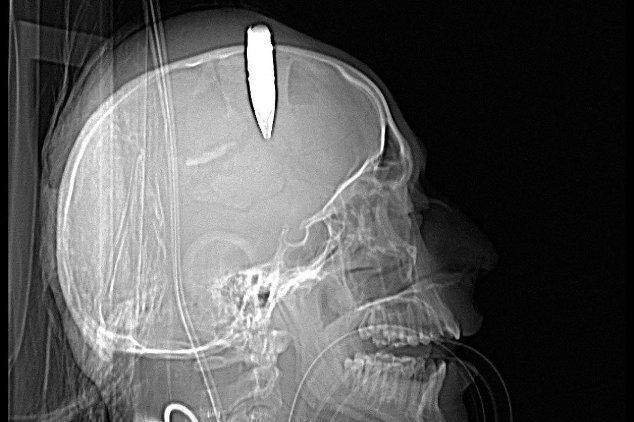

Sebuah amunisi aktif berukuran 14,5 milimeter tertancap di tengkorak seorang tentara Afganistan. Seperti tampak pada hasil CT Scan diatas. Seorang dokter militer dari Amerika Serikat telah berhasil mengeluarkan amunisi tersebut. Operasi dilakukan di Bagram Air Field Hospital - Afganistan Juni 2013 (Foto: U.S. Air Force)